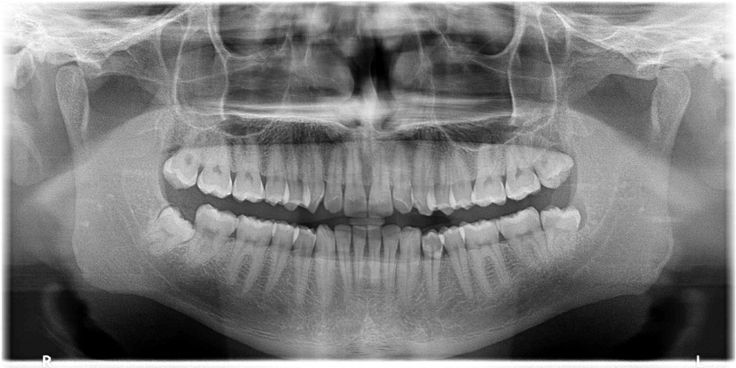

• Panoramic X-rays – Show a full view of the upper and lower jaws in a single image.

• OPG (Orthopantomogram) – Gives a panoramic view useful for wisdom tooth assessment, jaw issues, and more.

oral diagnosis and radiology